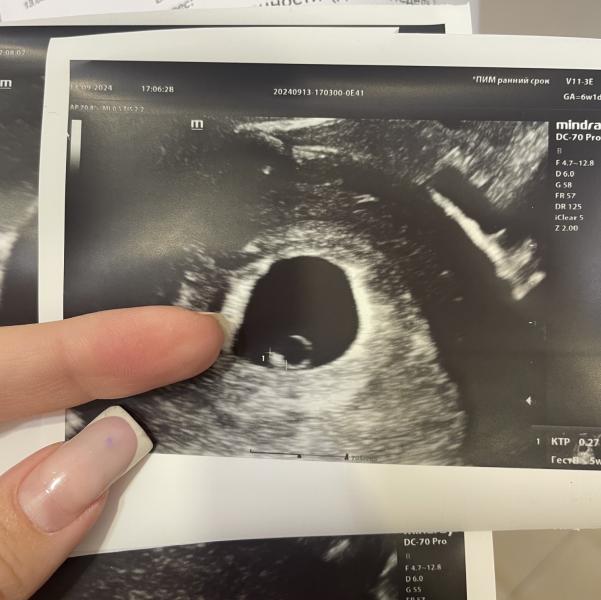

УЗИ 6,2

ПЯ 17мм

КТР 2,7мм ЧСС+

ЖМ 3,2мм

13.09.2024